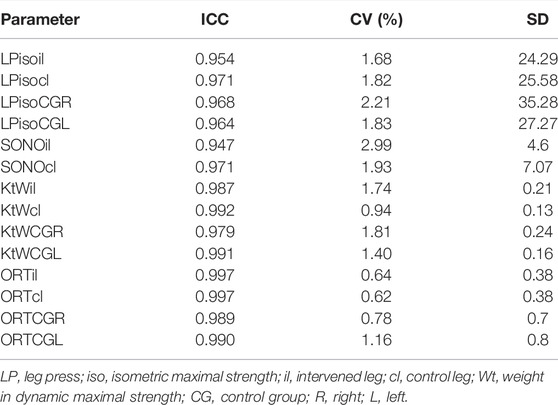

TABLE 2. Reliability for the pre-test values. ICC = intraclass correlation coefficient, CV = coefficient of variance, SD = Standard deviation.

Maximal Strength Measurement

Reliability was determined between best and second-best value and the “with-in day” reliability determined in this paper can be classified as high with a value of r = 0.98. ICC, CV and SD are listed in Table 2, too. Two persons evaluated the ultrasound images independently from each other.